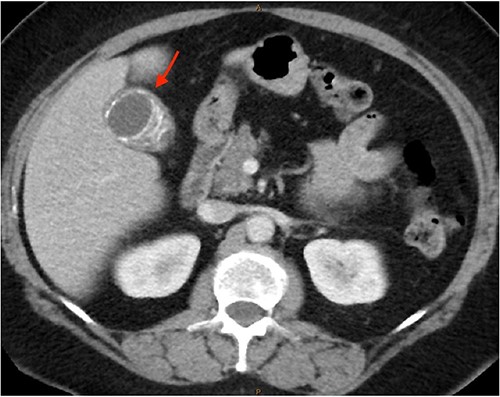

As only part of her gallbladder was imaged on the non-contrast CT lumbar spine, a repeat CT scan of her abdomen and pelvis with portal venous contrast was ordered. This showed semi-annular wall calcification at the gallbladder body suggestive for porcelain gallbladder and several calcified gallstones with largest measuring up to 32 mm (Figs 1–3). No gallbladder soft tissue mass was seen.

Semi-annular wall calcification at the gallbladder body—sagittal view.